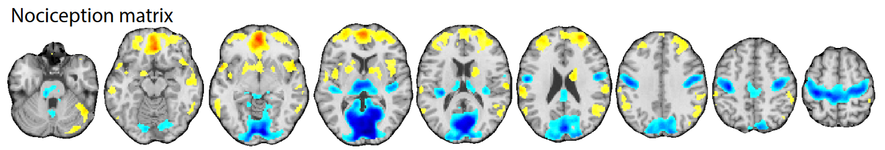

Aktuell existiert kein Standardmaß oder „Goldstandard“ zur Erfassung von Nozizeption im Menschen. Die Ursache hierfür liegt in der Schwierigkeit, die tatsächliche Nozizeption, also die neuronalen Vorgänge der Verarbeitung von Schmerz auslösenden Reizen am Menschen zu erfassen. Wir konnten dagegen zeigen, das seine Kombination bildgebender und elektrophysiologischer Messverfahren eine deutlich sensitivere und spezifischere Erfassung der nozizeptiven Verarbeitung am Menschen als zuvor möglich erlaubt.

Ziel ist, ein möglichst umfassendes, sensitives und spezifisches Messverfahren der Nozizeption für die Anwendung unter Allgemeinanästhesie bereitzustellen. Dazu muss der bisherige Messaufbau erweitert werden, um neben den aufsteigenden spinalen Bahnen, die an der nozizeptiver Verarbeitung beteiligt sind, auch die aus dem Hirnstamm absteigenden modulierenden Bahnen untersuchen zu können.